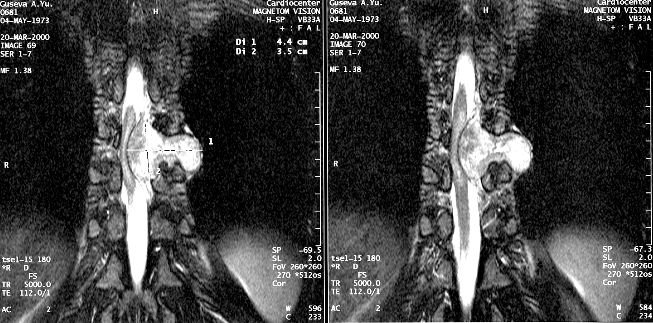

Основа диагностики — МРТ (рис. 2).

Рисунок 2. Эксрамедуллярная интрадуральная опухоль (невринома) поясничного отдела позвоночника (МРТ с контрастным усилением, Т1-взвешенные изображения)

Особую проблему представляют опухоли в виде «песочных часов», чаще невриномы, которые по мере роста распространяются из интрадурального пространства через межпозвонковое отверстие паравертебрально (рис. 3). Такие опухоли удаляются в 2 этапа: вначале обычно удаляется интрадуральная часть опухоли, затем при боковом расширении обычного срединного доступа или из нового доступа (например трансторакального) — экстраспинальный узел новообразования. При этом для радикального удаления опухоли вместе с ней приходится резецировать проходящий через спинальное отверстие не только чувствительный, но и двигательный корешок.

Рисунок 3. Эксрамедуллярная интрадуральная опухоль в форме «песочных часов» (невринома) грудного отдела позвоночника (МРТ с контрастным усилением, Т–1 взвешенные изображения)